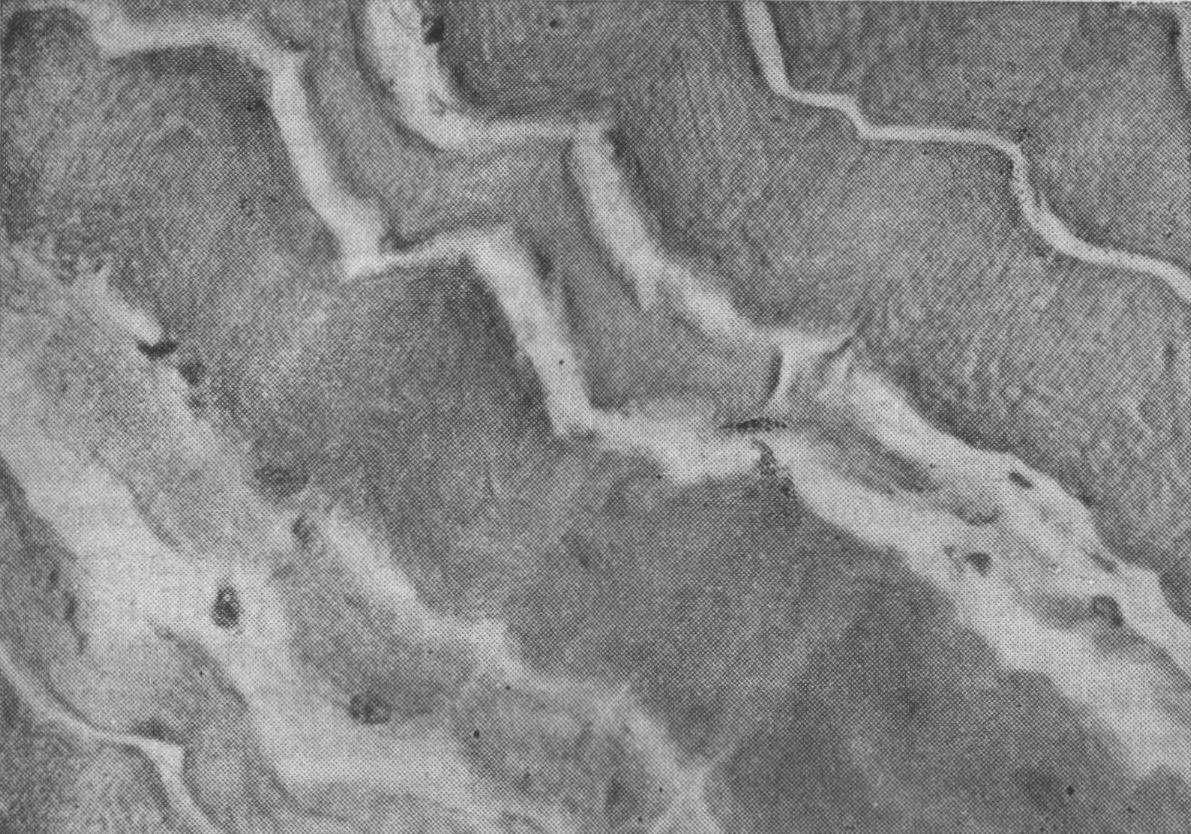

Рис. 62. Активность СДГ в волокнах собственно жевательной мышцы.

а — контрольная собака, б — через 14 сут после повышения межальвеолярной высоты прикуса на 6 мм; в — на 30-е сутки. Х80 (Иванов Л. И.).

тать, что первые сутки после повышения межальвеолярной высоты на 6 мм характеризовались снижением активности СДГ. На 3—5—7-е сутки имеет место подъем активности фермента выше исходных показателей. Затем следует период угасания компенсации (снижение активности на 14-е сутки), после которого следует снова подъем активности фермента (21-е сутки) с возвращением к норме (30-е сутки). Следовательно, в условиях длительного повышения межальвеолярной высоты на 6 мм в собственно жевательных мышцах уровень активности окислительного фермента (СДГ) циклически менялся, (рис. 62).

К 14-му дню эксперимента отмечено общее уменьшение содержания гликогена по сравнению с контрольными исследованиями и группой собак с повышением высоты прикуса на 2—-4 мм (рис. 63). При этом значительно увеличивалась распространенность диффузного окрашивания фуксинсернистой кислотой мышечных волокон и стенок сосуда. Разная морфологическая характеристика гликогена, по-видимому, отражает в данном случае усиление гликогенолиза в связи с повышенной функциональной нагрузкой.